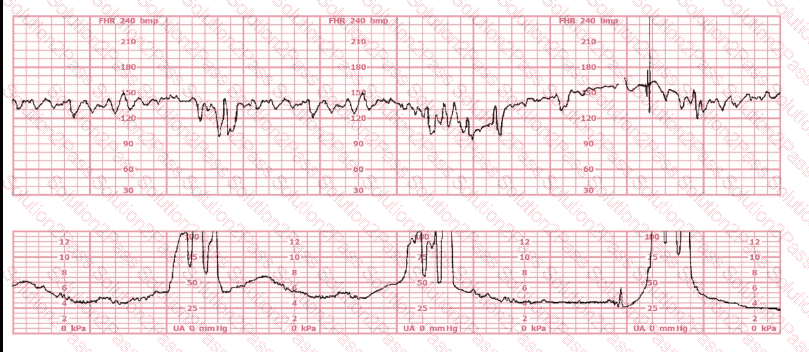

The decelerations seen in the fetal monitoring tracing shown are best described as: